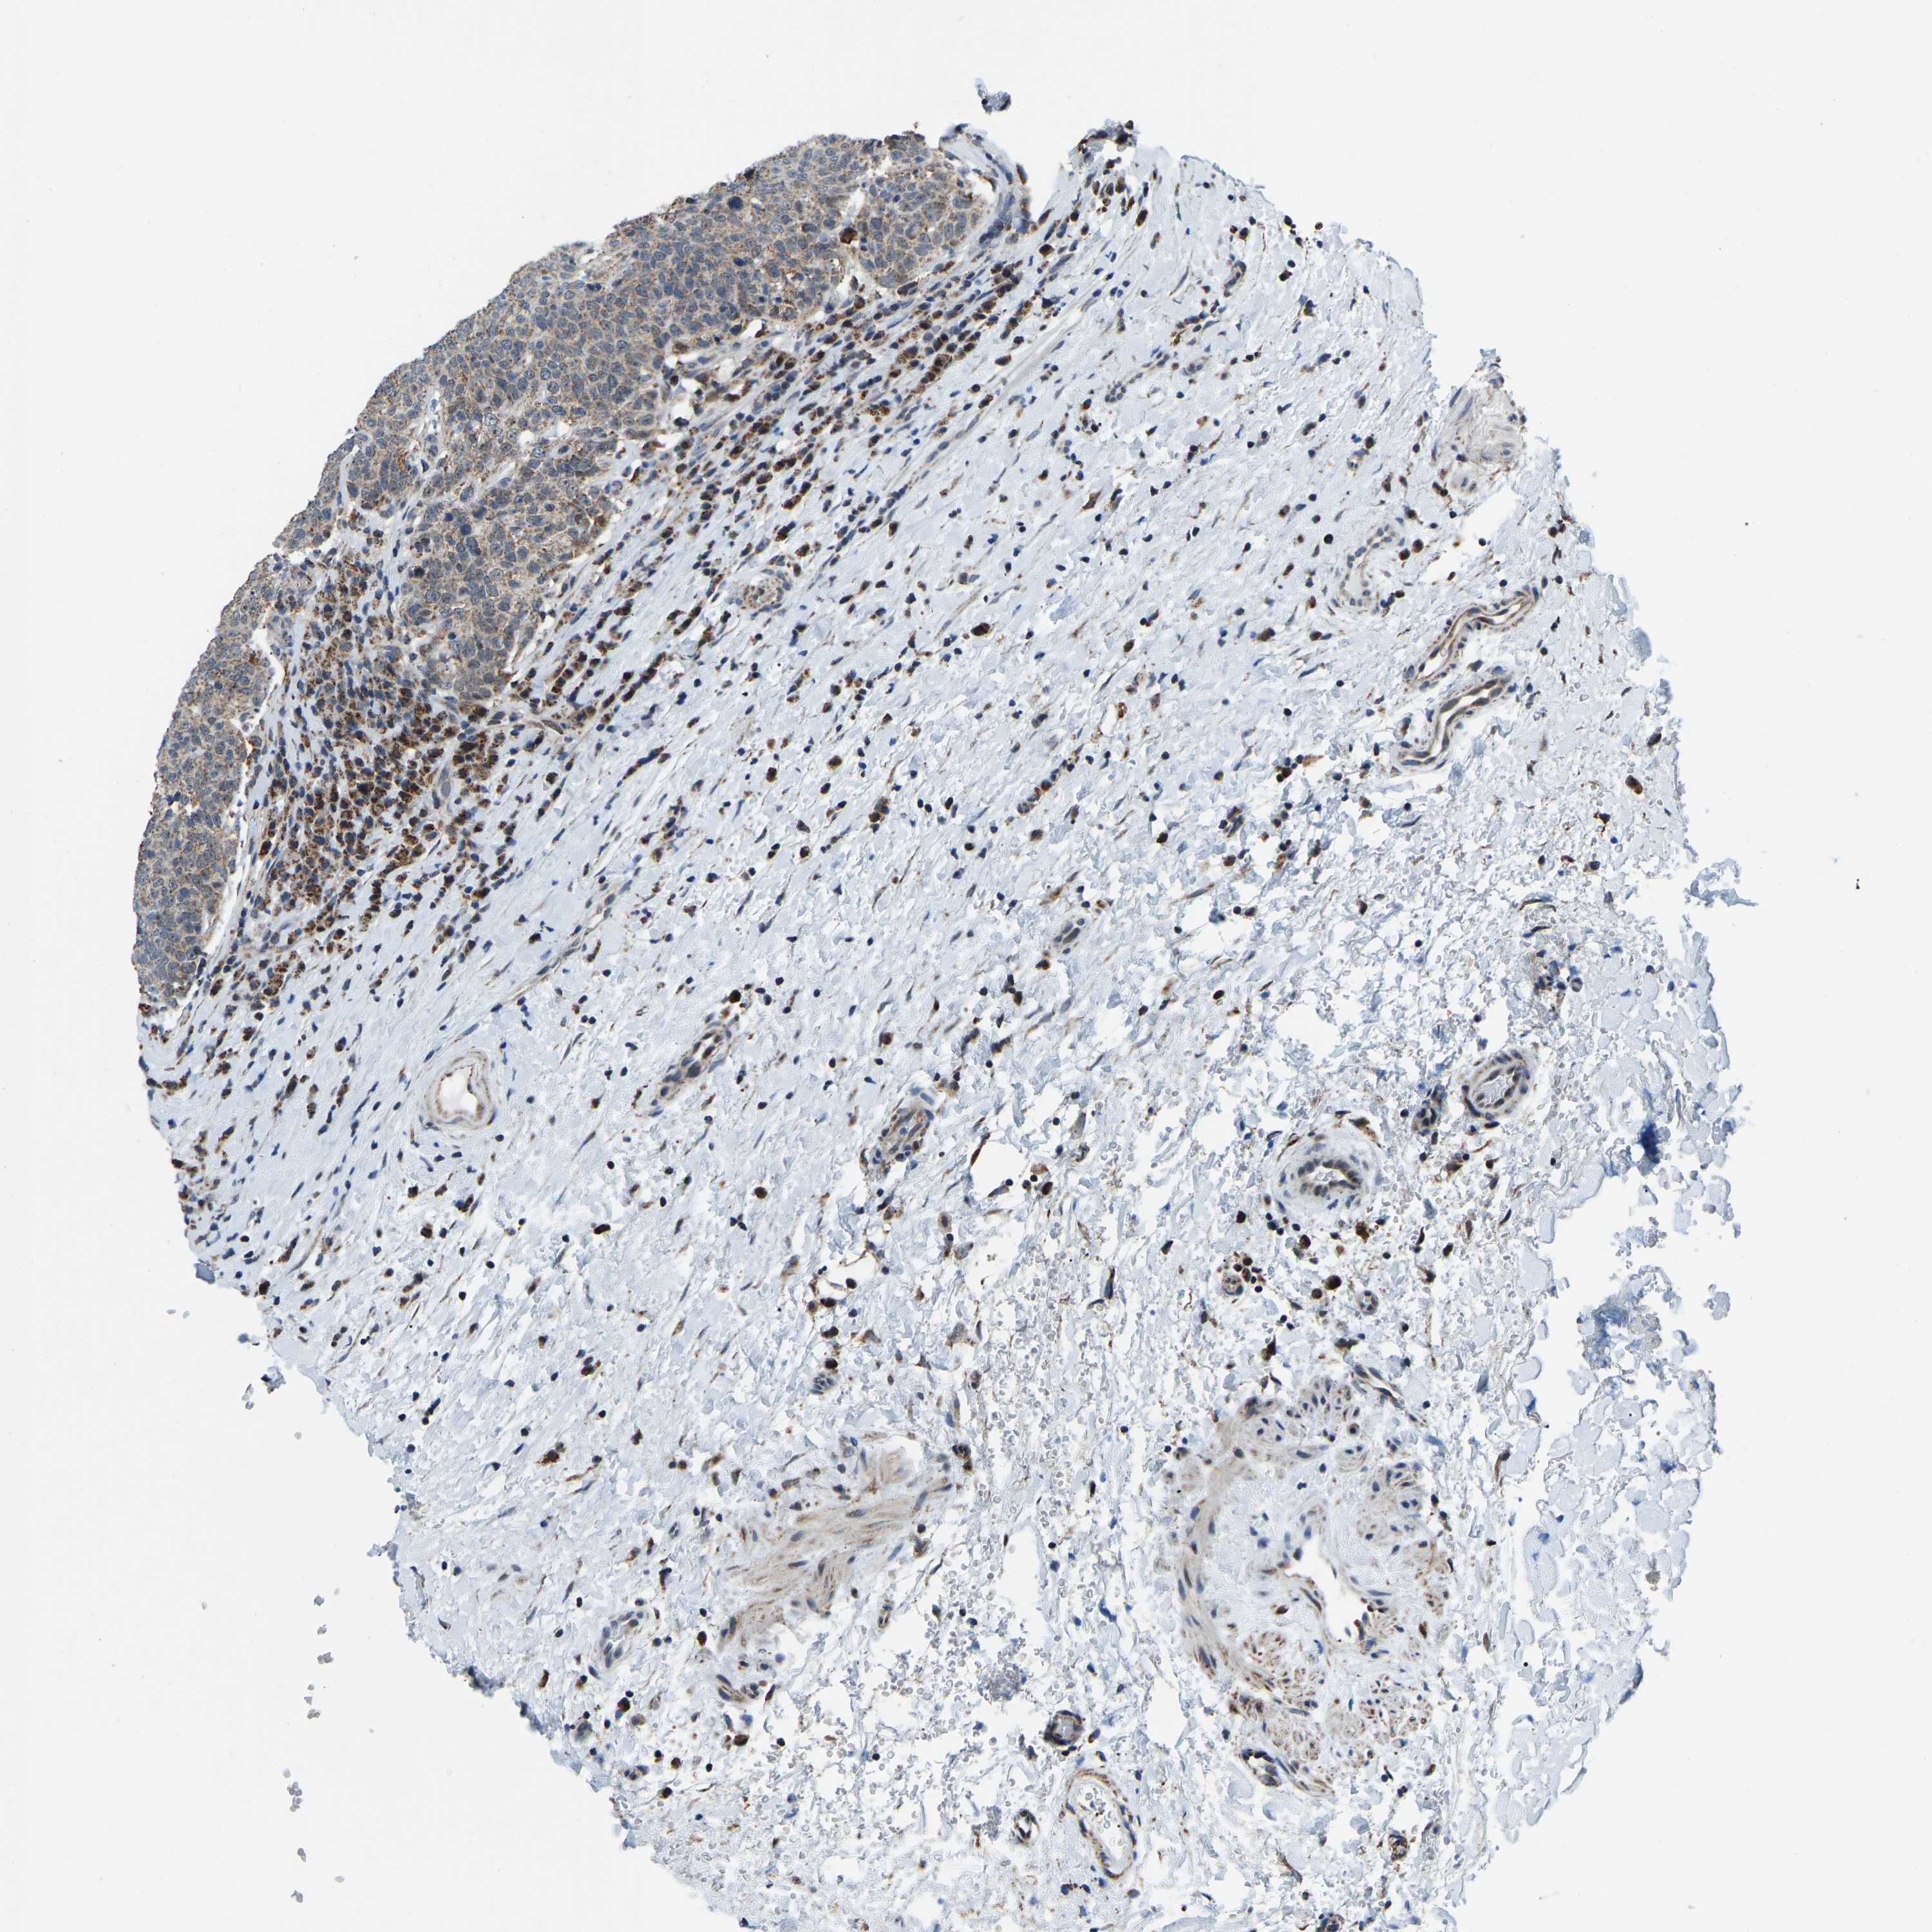

HEAD AND NECK CANCER - Protein expressioni

A mouse-over function shows sample information and annotation data. Click on an image to view it in a full screen mode. Samples can be filtered based on level of antibody staining by selecting one or several of the following categories: high, medium, low and not detected. The assay and annotation is described here.

Antibody stainingi

Antibody staining in the annotated cell types in the current human tissue is reported as not detected, low, medium, or high, based on conventional immunohistochemistry profiling in selected tissues. This score is based on the combination of the staining intensity and fraction of stained cells.

Each image is clickable and will lead to virtual microscopy that enables deeper exploration of all samples and also displays staining intensity scores, fraction scores and subcellular localization as well as patient and tissue information for each sample.

Antibody HPA019232

Antibody HPA021497

Antibody HPA021768

Staining

High

Medium

Low

Not detected

Intensity

Strong

Moderate

Weak

Negative

Quantity

>75%

75%-25%

<25%

None

Location

Nuclear

Cytoplasmic/membranous

Cytoplasmic/membranous,nuclear

Squamous cell carcinoma, NOS

Squamous cell carcinoma, metastatic, NOS

Adenocarcinoma, NOS